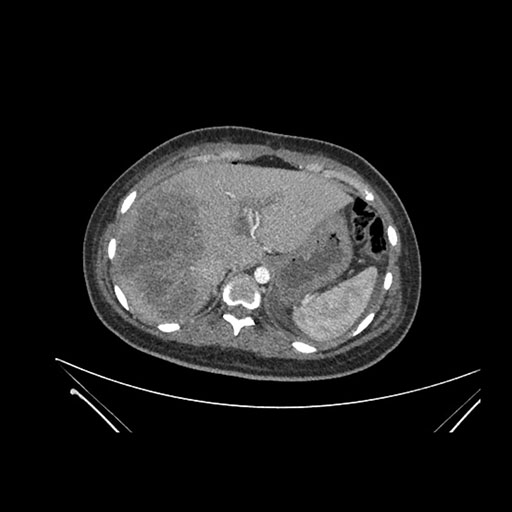

Coronal Arterial

Coronal Venous

Imaging analysis

Based on initial findings, which issue(s) would you be most concerned about?